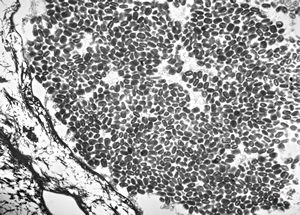

M,50y. | Pneumocystis carinii